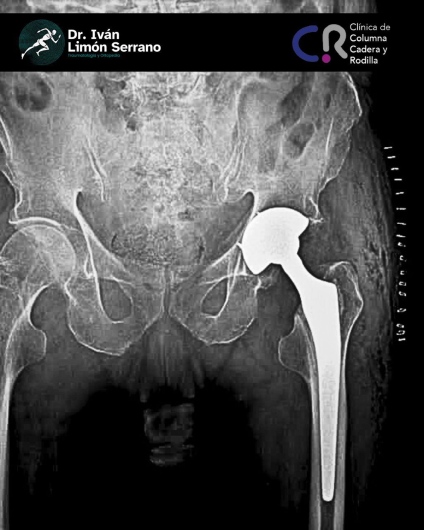

• Prótesis de cadera

• Cirugía cadera

• Artroscopia de cadera